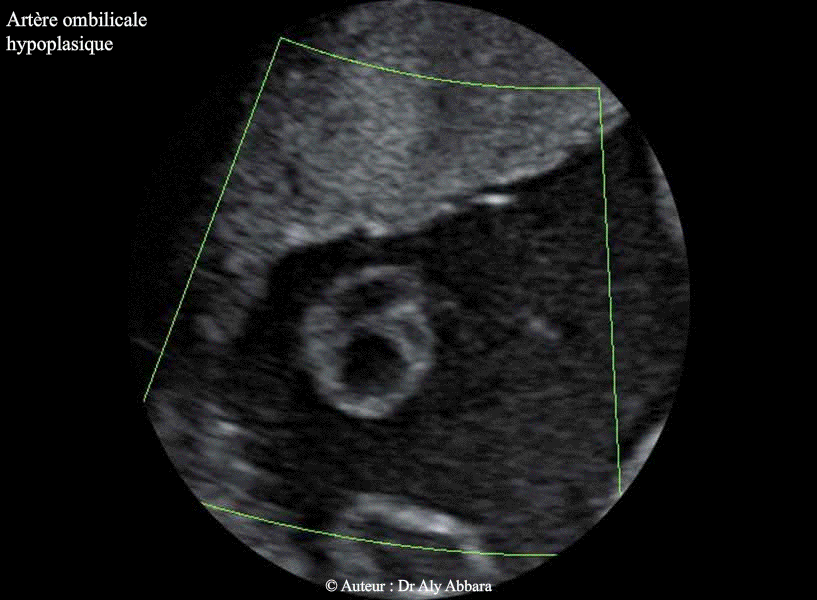

Cordon ombilical - Artère ombilicale hypoplasique

• Images échographiques montrant une hyperplasie d'une des deux artères ombilicales identifiable sur la totalité de la longueur du cordon ombilical.

• Il s'agit du cordon ombilical d'un fœtus de 34 SA d'âge in-utero, morphologiquement présentant une volumineuse omphalocèle contenant la totalité de son foie, sans aucune d'autre anomalie exceptée cette hypoplasie d'une artère ombilicale ; caryotype normal.

• La fréquence de l'hypoplasie d'une des deux artères ombilicales est de l'ordre de 0,01% des naissances.